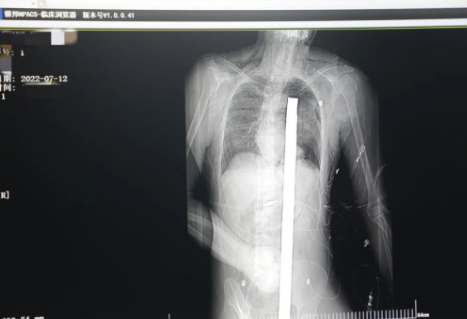

突發(fā)!太疼了,1.2米長的螺紋鋼從男子會陰部垂直穿入胸腔......7月12日下午16時10分,西安一處工地的一名26歲工友,不慎從10多米的高空墜落,不幸的是工地上一根直徑3厘米的螺紋鋼從男子會陰部垂直穿入體內(nèi),工地上的工友們小心翼翼地將連著的鋼筋截?cái)?。情況危急,立即送往西安國際醫(yī)學(xué)中心醫(yī)院急救中心,此時正是下午17時00分。

時間就是生命!此時,西安國際醫(yī)學(xué)中心醫(yī)院展開了一場與生命賽跑的搶救,第一時間開辟綠色通道,急診X光片及CT顯示:異物經(jīng)會陰部貫穿盆腔、腹腔到達(dá)左側(cè)胸腔主動脈弓水平。醫(yī)院創(chuàng)傷中心立即啟動應(yīng)急預(yù)案,劉延彤副院長親臨指揮,下午17點(diǎn)48分,當(dāng)患者被送達(dá)手術(shù)室,胸外、心外、肝膽外科、胃腸外科,泌尿外科及麻醉科等多學(xué)科專家聯(lián)手對這名工友進(jìn)行“縱劈胸骨 前外側(cè)開胸探查 氣管及主支氣管修補(bǔ) 肺修補(bǔ) 血胸清除 開腹探查止血 腹膜后及盆腔探查......”手術(shù)。

情況緊急!術(shù)中探查后發(fā)現(xiàn),長120cm直徑3cm的螺紋鋼經(jīng)患者右側(cè)會陰部穿入,傷及直腸,途徑膀胱后方,左側(cè)髂總動靜脈之間傷及左腎后,經(jīng)胰腺后方在肝脾之間穿破膈肌,在下肺靜脈前方穿入左肺穿破氣管及左右主支氣管膜部,止于主動脈弓下水平,穿入體內(nèi)的部分達(dá)到75cm。